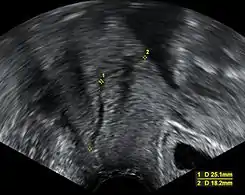

![]() Imagen de ultrasonido midiendo la longitud del cuello uterino en una mujer embarazada con sospecha de insuficiencia cervical | ||

La incompetencia cervical puede ser desafiante y está basada en antecedentes de dilatación cervical no dolorosa normalmente después del primer trimestre y sin contracciones o trabajo de parto y ante la ausencia de otra patología evidente. Además de estos antecedentes, se suele utilizar la longitud cervical medida en el segundo trimestre para identificar el acortamiento cervical con el uso de ultrasonido.[3] Aun así, una corta longitud cervical ha sido pronóstico o marcador de un parto prematuro y no necesariamente de incompetencia cervical. Otras pruebas diagnósticas sugeridas y que aún carecen de validación incluyen la histerosalpingografía e imágenes radiográficas de tracción por balón del cuello uterino, la valoración del patulous cervical con dilatadores de Hegar o Pratt, el uso de una prueba de elasticidad con balón, y uso de graduado de dilatadores cervicales para calcular un índice de resistencia cervical.[1]

Normalmente, el cuello uterino tiene al menos 30 mm de longitud. La definición de incompetencia varía. Aun así, una definición tradicional es aquella con una longitud cervical menor de 25 mm antes o para el momento de las 24 semanas de edad gestacional El riesgo de parto pretermino es inversamente proporcional a la longitud cervical:[4]